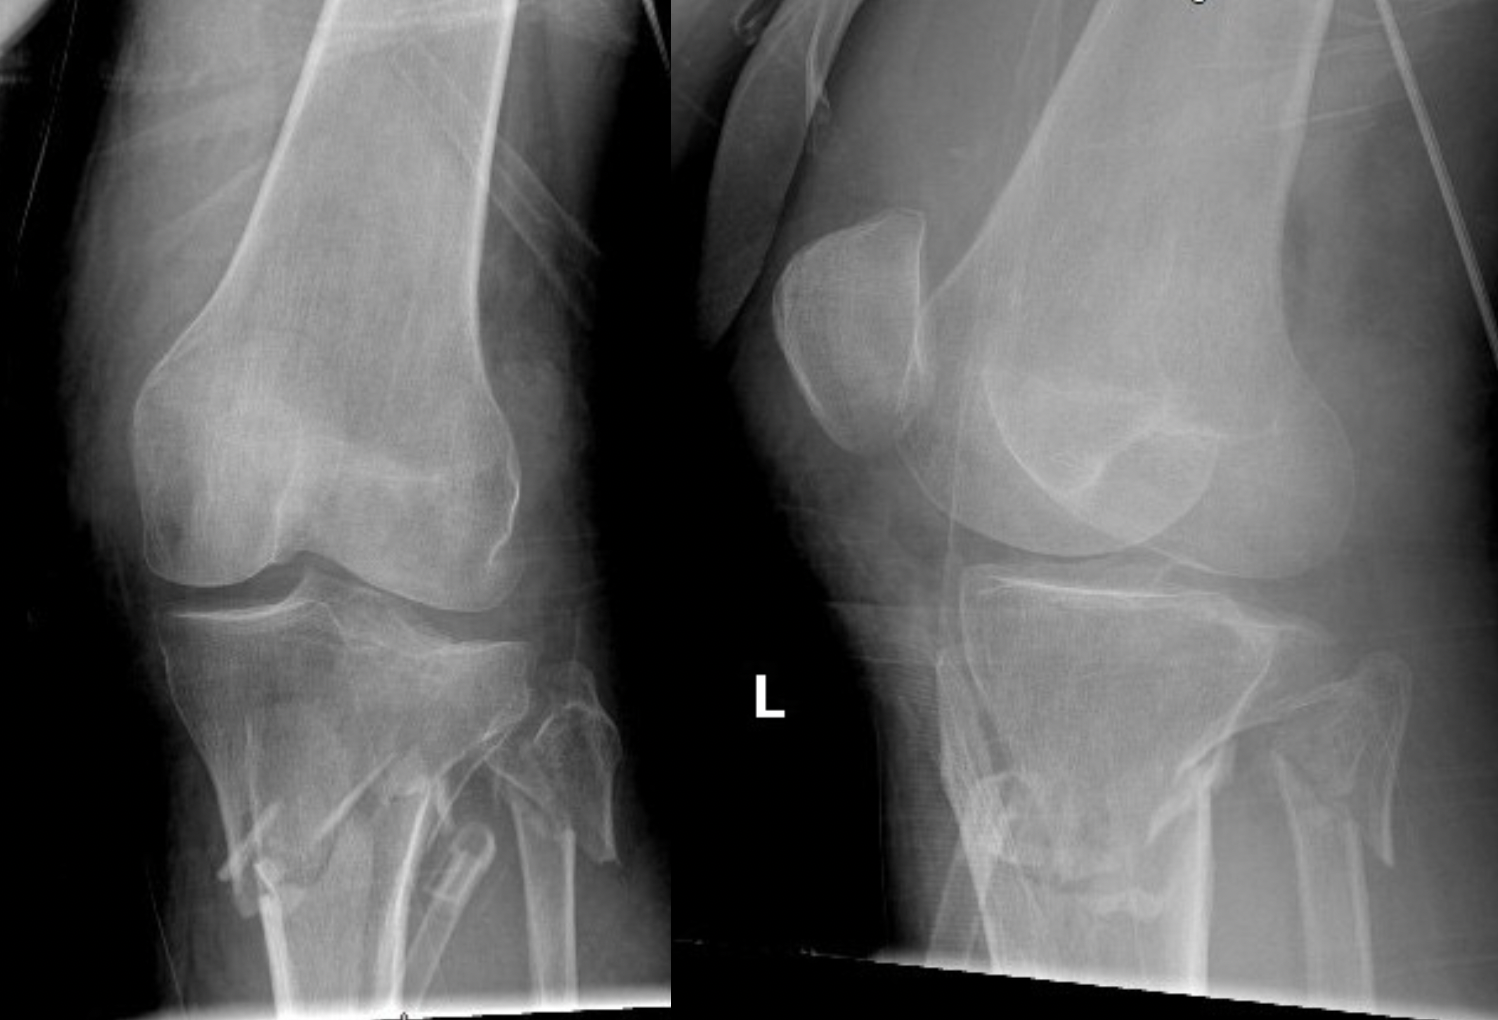

Deformity

- abductors/hamstrings (pes) = varus of proximal fragment = valgus of fracture

- patella tendon = extension of proximal fragment = procurvatum of fracture

Characteristic valgus deformity with extension of the proximal fragment